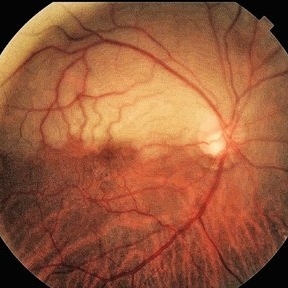

Retina Images (13 files)

Retina Images (13 files)

BRAO (3 files)

BRAO (3 files)